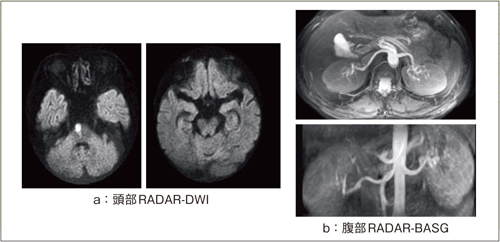

RADARは,SE,FSE,FIR,DWI,BASG(バランス系高速撮像)といった幅広いシーケンスに適用可能です。図3aはRADARを適用した頭部DWIの画像例ですが,歪みが少ない画像が得られています。図3bは腹部腎動脈のBASGによる3D MIP像とMPR像で,呼吸のアーチファクトが低減されています。

図3 RADARのシーケンス適用例